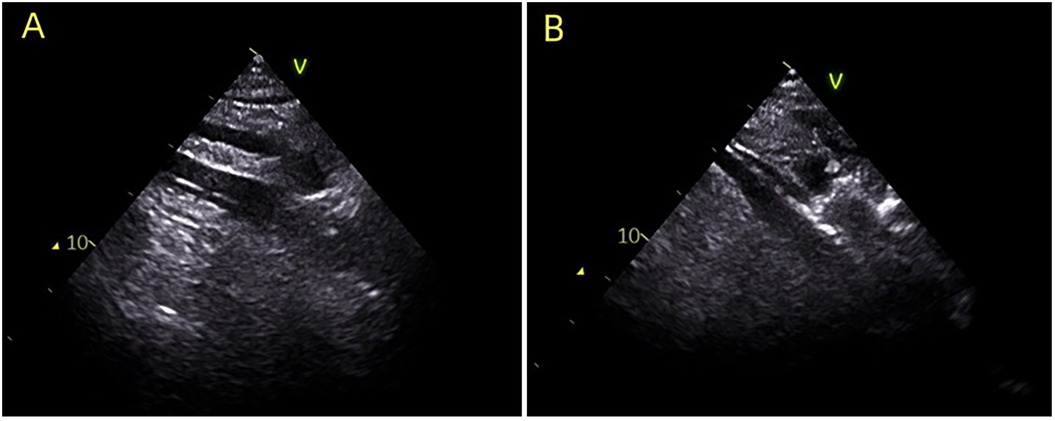

Patients were categorized into two groups based on the method of venous cannulation positioning: an ultrasound-guided group (UG, n = 23) and a body surface landmark group (BSL, n = 25). As shown in Figure 1, in the UG group, real-time ultrasound guidance using a phased-array cardiac probe was employed to track guidewire advancement into the right atrium, and the cannula was subsequently adjusted to ensure placement in the mid-right atrium. In contrast, the BSL group underwent cannulation based solely on anatomical surface landmarks, with guidewire insertion and cannula depth estimated by external measurements, without the aid of imaging guidance.

Figure 1. During the establishment of ECMO, ultrasound guidance was utilized to ensure accurate placement of the venous cannula in the ideal position. (A) Indicates the guide wire positioned in the right atrium; (B) illustrates the venous cannula guided into the right atrium.